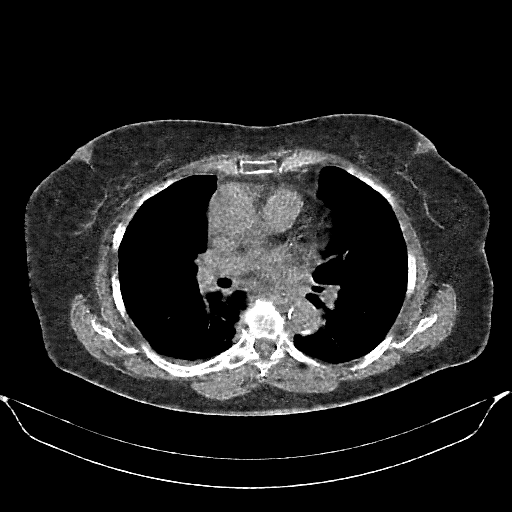

Generated VENOUS CT scan (A→B translation)

No window - Raw intensity values

Lung window (WL -600, WW 1500 β†’ Low βˆ’1350, High +150)

Mediastinum window (WL 40, WW 400 β†’ Low βˆ’160, High +240)